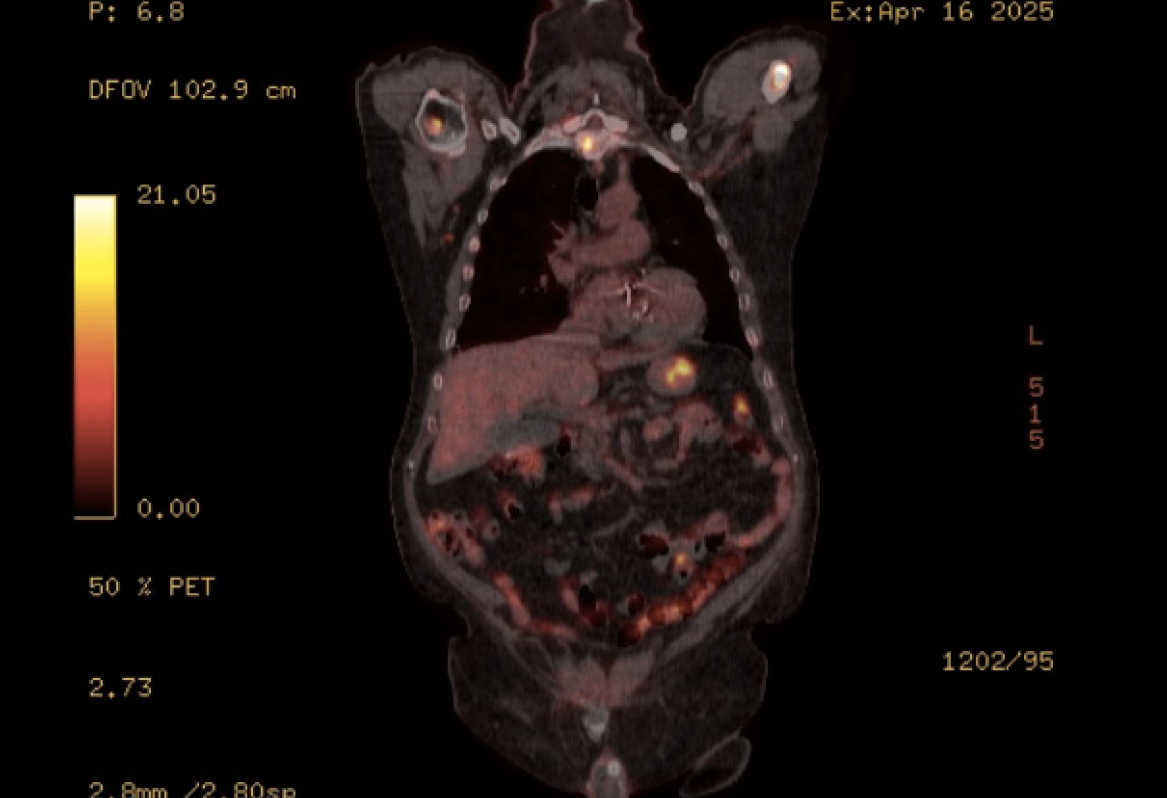

PET scan revealed disseminated, mixed, predominantly lytic bone metastases throughout the axial and appendicular skeletons, including throughout the spine, pelvis, bilateral mid to proximal humeri and femora, bilateral ribs, sternum and bilateral scapulae. There was no definite fluorodeoxyglucose-avid primary neoplasm, particularly in the lung. There was non-specific mild to moderate heterogeneous uptake in the stomach, most intensely in the proximal stomach along the greater curvature, and distal stomach along the lesser curvature and pylorus (Figure 1). There was no significant focal fluorodeoxyglucose uptake seen elsewhere to suggest other metastatic disease. Following this PET result, the patient underwent a gastroscopy with gastric nodule biopsies to further investigate the malignant process. Multiple 10-20 mm semi-sessile polyps were noted in the gastric fundus, antrum, greater and lesser curvature and the incisura (Figure 2). There were no other overt lesions identified.